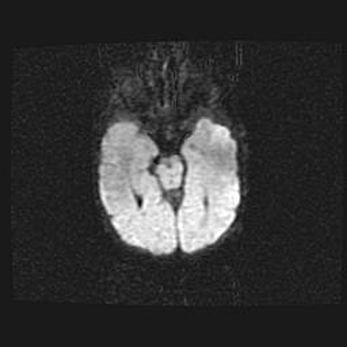

Сообщающаяся гидроцефалия. Кистозная энцефаломаляция головного мозга.

Возраст: 3 месяца 4 дня

Вес: 3100 г

Пол: женский

Окружность головы: 34 см

Срок гестации: 31 неделя

Кистозная энцефаломаляция головного мозга - одна из форм поражения головного мозга в детском возрасте. Характеризуется возникновением множественных и распространённых кист в коре, белом веществе и подкорковых образованиях головного мозга у плодов, новорождённых и детей раннего возраста. Развитие кистозной энцефаломаляции связано с внутриутробной асфиксией и гипотонией, родовой травмой, тромбозом синусов, пороками развития сосудов, инфекциями, сепсисом и другими причинами. Наиболее значимые инфекционные агенты: вирусы простого герпеса, цитомегалии, краснухи, токсоплазмы, энтеробактерии, золотистый стафилококк и другие.